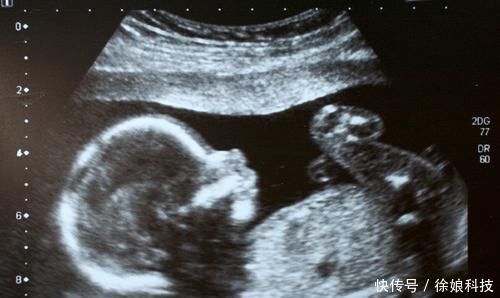

3、语言胎教

语言胎教要由父母二人分别担任不同的角色。妈妈的声波是高频 ,爸爸的声波是中低频,这样能从不同方面刺激胎儿大脑的发育。所以准爸爸千万别以为跟孩子讲故事聊天仅仅是妈妈一个人的事情。

父母可以跟孩子讲述故事,诗歌,童话,但是一定要用简单的语言,像刚开始教孩子说话那样。这样有助于胎儿神经回路形成,激发大脑发育。